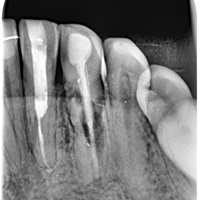

Dziesieć lat po wykonaniu mostu pacjent zgłosił się z recesją dziąsła i próchnicą korzenia. Zamiast ekstrakcji wykonano hemisekcję i nowy most.